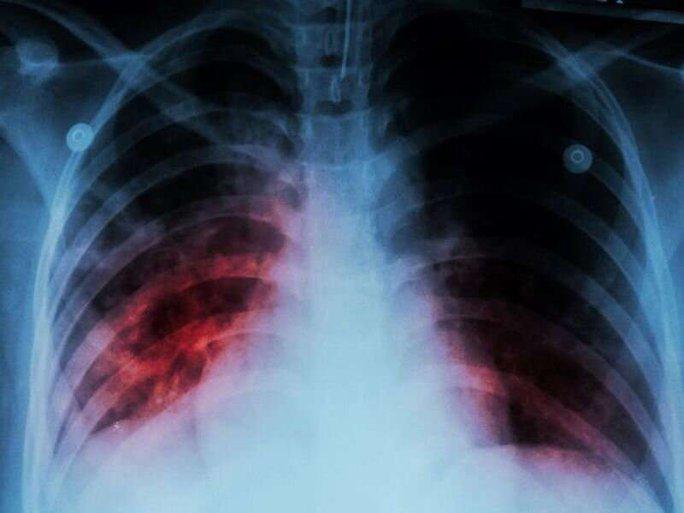

Old  Default WHO: Một bệnh cũ trỗi dậy sau 20 năm, đang gây tử vong nhiều hơn COVID-19

Theo báo cáo của Tổ chức Y tế thế giới (WHO), năm vừa qua là lần đầu tiên sau gần 2 thập kỷ số ca mắc bệnh lao, số ca lao đa kháng thuốc và tử vong do lao đều tăng.

Báo cáo được phát hành nhân Ngày Thế giới pḥng chống lao (24-3) của WHO cho biết hàng năm vẫn có trung b́nh 1,6 triệu người chết do bệnh lao.

Con số này c̣n cao hơn số tử vong do một bệnh hô hấp đáng sợ khác hiện nay - COVID-19 - với báo cáo tử vong hiện đă về dưới 10.000 ca/tuần.

Đáng lo hơn, theo Tổng Giám đốc WHO Tedros Adhanom Ghebreyesus, đại dịch COVID-19 cùng với các cuộc khủng hoảng đang diễn ra như xung đột, mất an ninh lương thực, biến đổi khí hậu... đă đảo ngược tiến bộ đạt được trong nhiều năm trong cuộc chiến chống bệnh lao, khiến năm 2022 trở thành năm đầu tiên sau gần 2 thập kỷ căn bệnh này gia tăng cả số ca mắc, số ca lao đa kháng thuốc và số ca tử vong.